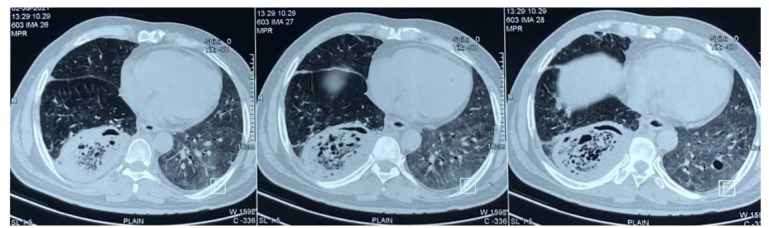

Results: Based on the findings, 8 (16%) out of 50 patients with rhino-orbital mucormycosis, had associated possible or probable pulmonary mucormycosis. All 8 patients were diabetics and had characteristic CT chest findings while only half of them had positive sputum microscopy. A higher prevalence of probably disseminated COVID-19-associated mucormycosis was noted among 51-60-year-old males with the use of corticosteroids and oxygen for COVID-19 therapy. The mortality rate was 100% in probably disseminated mucormycosis, 50% in possible disseminated mucormycosis, and only 9.5% in isolated rhino-orbital mucormycosis.

Abstract Image